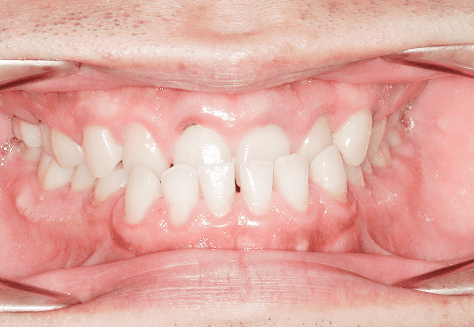

M.U

治療前

治療後

主訴

下の歯が特にガタガタなのが気になる。上の前歯が1本反対になっている。

診断

下顎前突・叢生・反対咬合

年齢/性別

20代/男性

抜歯部位

非抜歯

使用装置

上下インビザライン(PBM使用)

保定装置

ビベラリテーナー

料金

初回資料採得・・・・・・・30,000円

診断料・・・・・・・・・・33,000円

動的治療終了時資料採得・・5,500円 -

基本料金

950,000円

診察料金

5,500円×16回

治療期間

1年7カ月